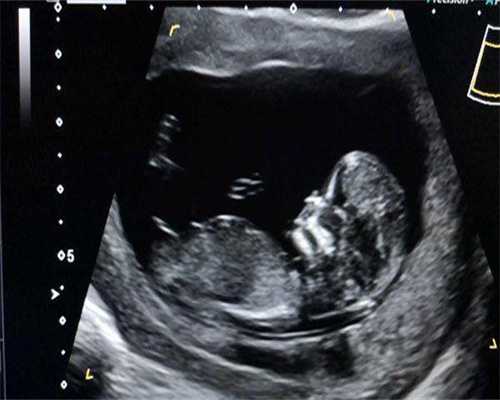

女性的最佳生育年龄是在23-30岁之间。34岁做试管婴儿成功率还是不错的,一般都能达到40%-50%左右,34岁生育已经算是大龄生育了,这个年龄如果要做试管生育的话那就一定要趁早,不能再拖了,因为女性年龄是影响试管成功率的最主要因素。34岁做试管婴儿成功率高低关键看女性的身体素质、卵子的质量、子宫内膜这三点,如果这三点都还不错的话,那么试管婴儿的成功率也会相对高一点,如果这些方面不行不仅试管的成功率会降低,还可能失去做试管婴儿的机会。